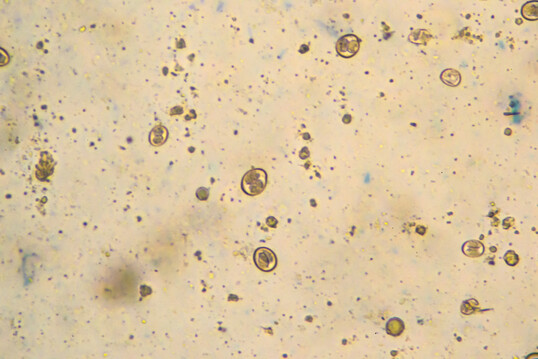

Kokzidiose lauert nicht nur in Geflügelställen – sie gedeiht dort regelrecht. Wird sie nicht kontrolliert, schädigt sie die Darmgesundheit, hemmt das Wachstum und begünstigt teure Sekundärinfektionen.